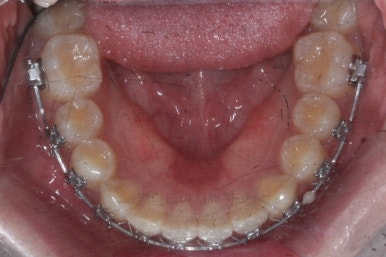

마찬가지로 부산교정치과 키다리아저씨치과에 처음 내원하셨을 당시의 입안 모습입니다.

또 다른 문제는 위아래 앞니가 매우 많이 겹쳐져 있어서 아래 앞니가 거의 보이지 않는다는 점입니다.

미적인 문제 뿐만이 아니라 기능적인 문제도 만들어낼 수 있어서 고쳐주는 것이 좋아요.

작은 앞니가 왜소치이다 보니 윗니에는 틈이 남아있고 교합도 조금 엉성한 모습이에요.

왜소치의 사이즈가 위아래 교합을 맞춰주는데 방해가 된다고 판단하여 왜소치를 크게 해주기로 결정했습니다.

우선 현재 상태에서는 사이즈를 크게 하지 못하기 때문에 왜소치 좌우로 틈새를 만들어주기로 했습니다.